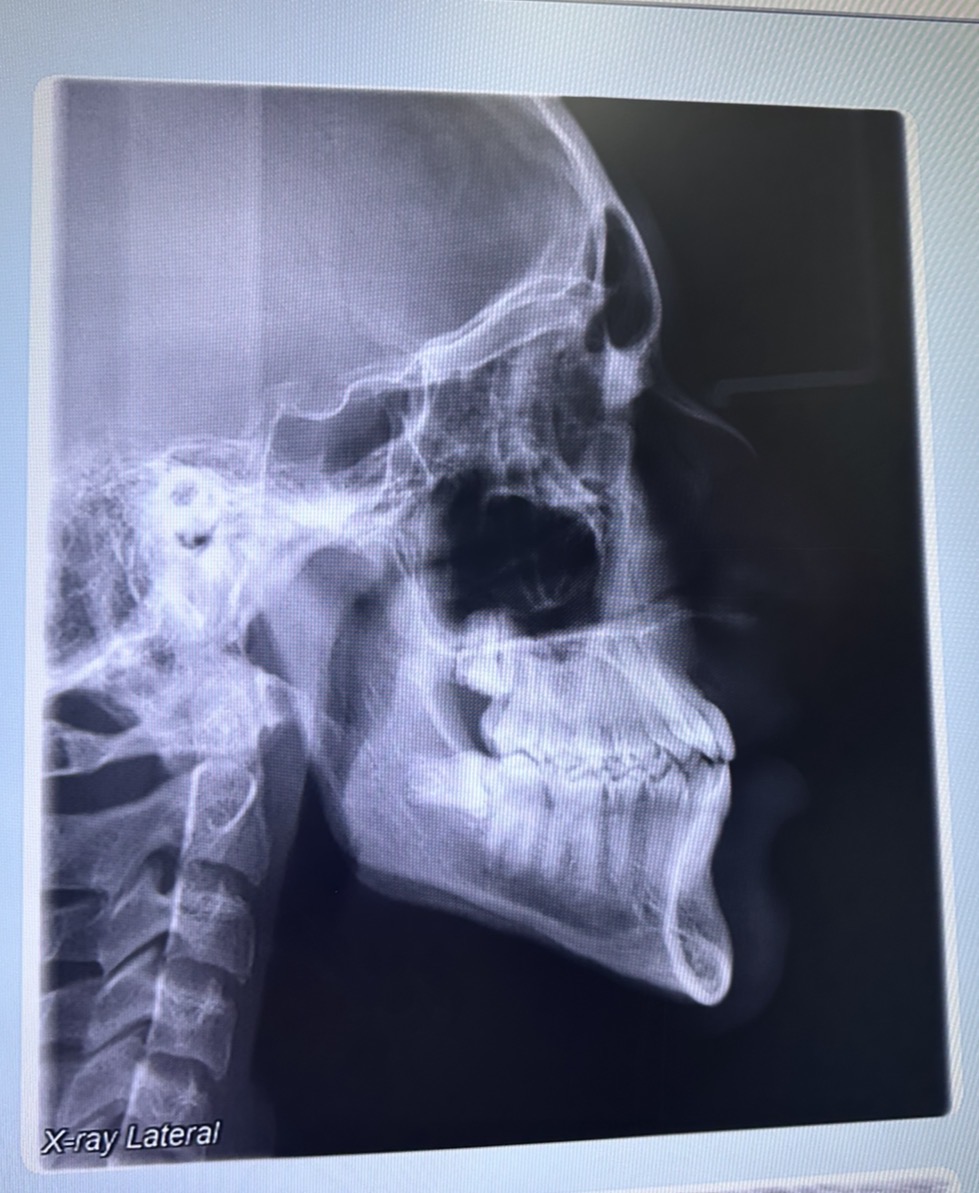

Should I get a lefort 1 I have 49mm palate so palate expansion to move my maxilla isn’t possible? What surgery’s should I get?